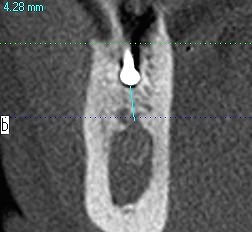

埋入前のCTの審査になります

これと術中の審査のCTがすべてです

最初のラウンドドリリングのラウンドバーにて下顎管の距離を測る

CTを取ります